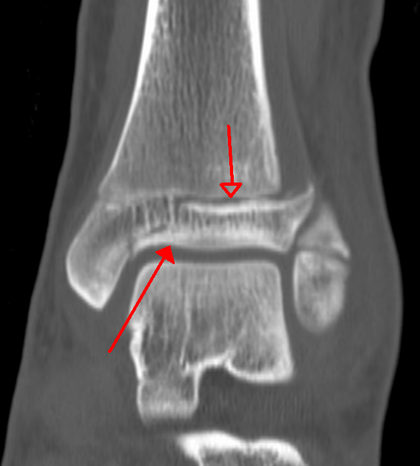

КТ

КТ трёхплоскостного перелома

При травмах стопы и голеностопа использование КТ предлагается как метод для оценки пассивной подсистемы. Это быстрая методика, и она может использоваться во время операции. Компьютерная томография с нагрузкой (WBCT) позволяет измерять и анализировать положение костей стопы и голеностопа и их деформации.[21] Рекомендации по использованию КТ и WBCT включают:

• Для оценки переломов в области голеностопного сустава.[2]

• Для оценки синдесмотического восстановления. Компьютерная томография с нагрузкой (WBCT) доказала свою более высокую надежность.[22]

• Для предсказания синдесмотических травм при переломах голеностопа.[23]

• Для диагностики скрытой нестабильности Лисфранка.[25]